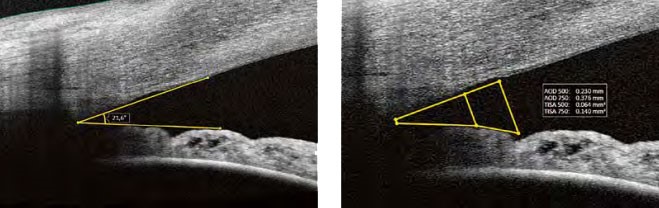

АНАЛІЗ ПЕРЕДНЬОГО СЕГМЕНТУ

Завдяки додатковому адаптеру переднього сегмента ASA-1, Xephilio OCT-A1 надає вам можливість проаналізувати та задокументувати передній сегмент без необхідності додаткового дослідження. Включений пакет вимірювань дозволяє швидко та легко оцінити стандартні параметри.

Аналіз товщини рогівки на Xephilio OCT-A1 представлений у вигляді карт товщини рогівки та товщини епітелію, включаючи корнеальні сітки, а також числової таблиці.

Програма для аналізу переднього сегмента дозволяє виміряти відстань між двома точками, довільні кути, а також значення AOD (відстань відкриття кута) та TISA іридо-трабекулярний простір.